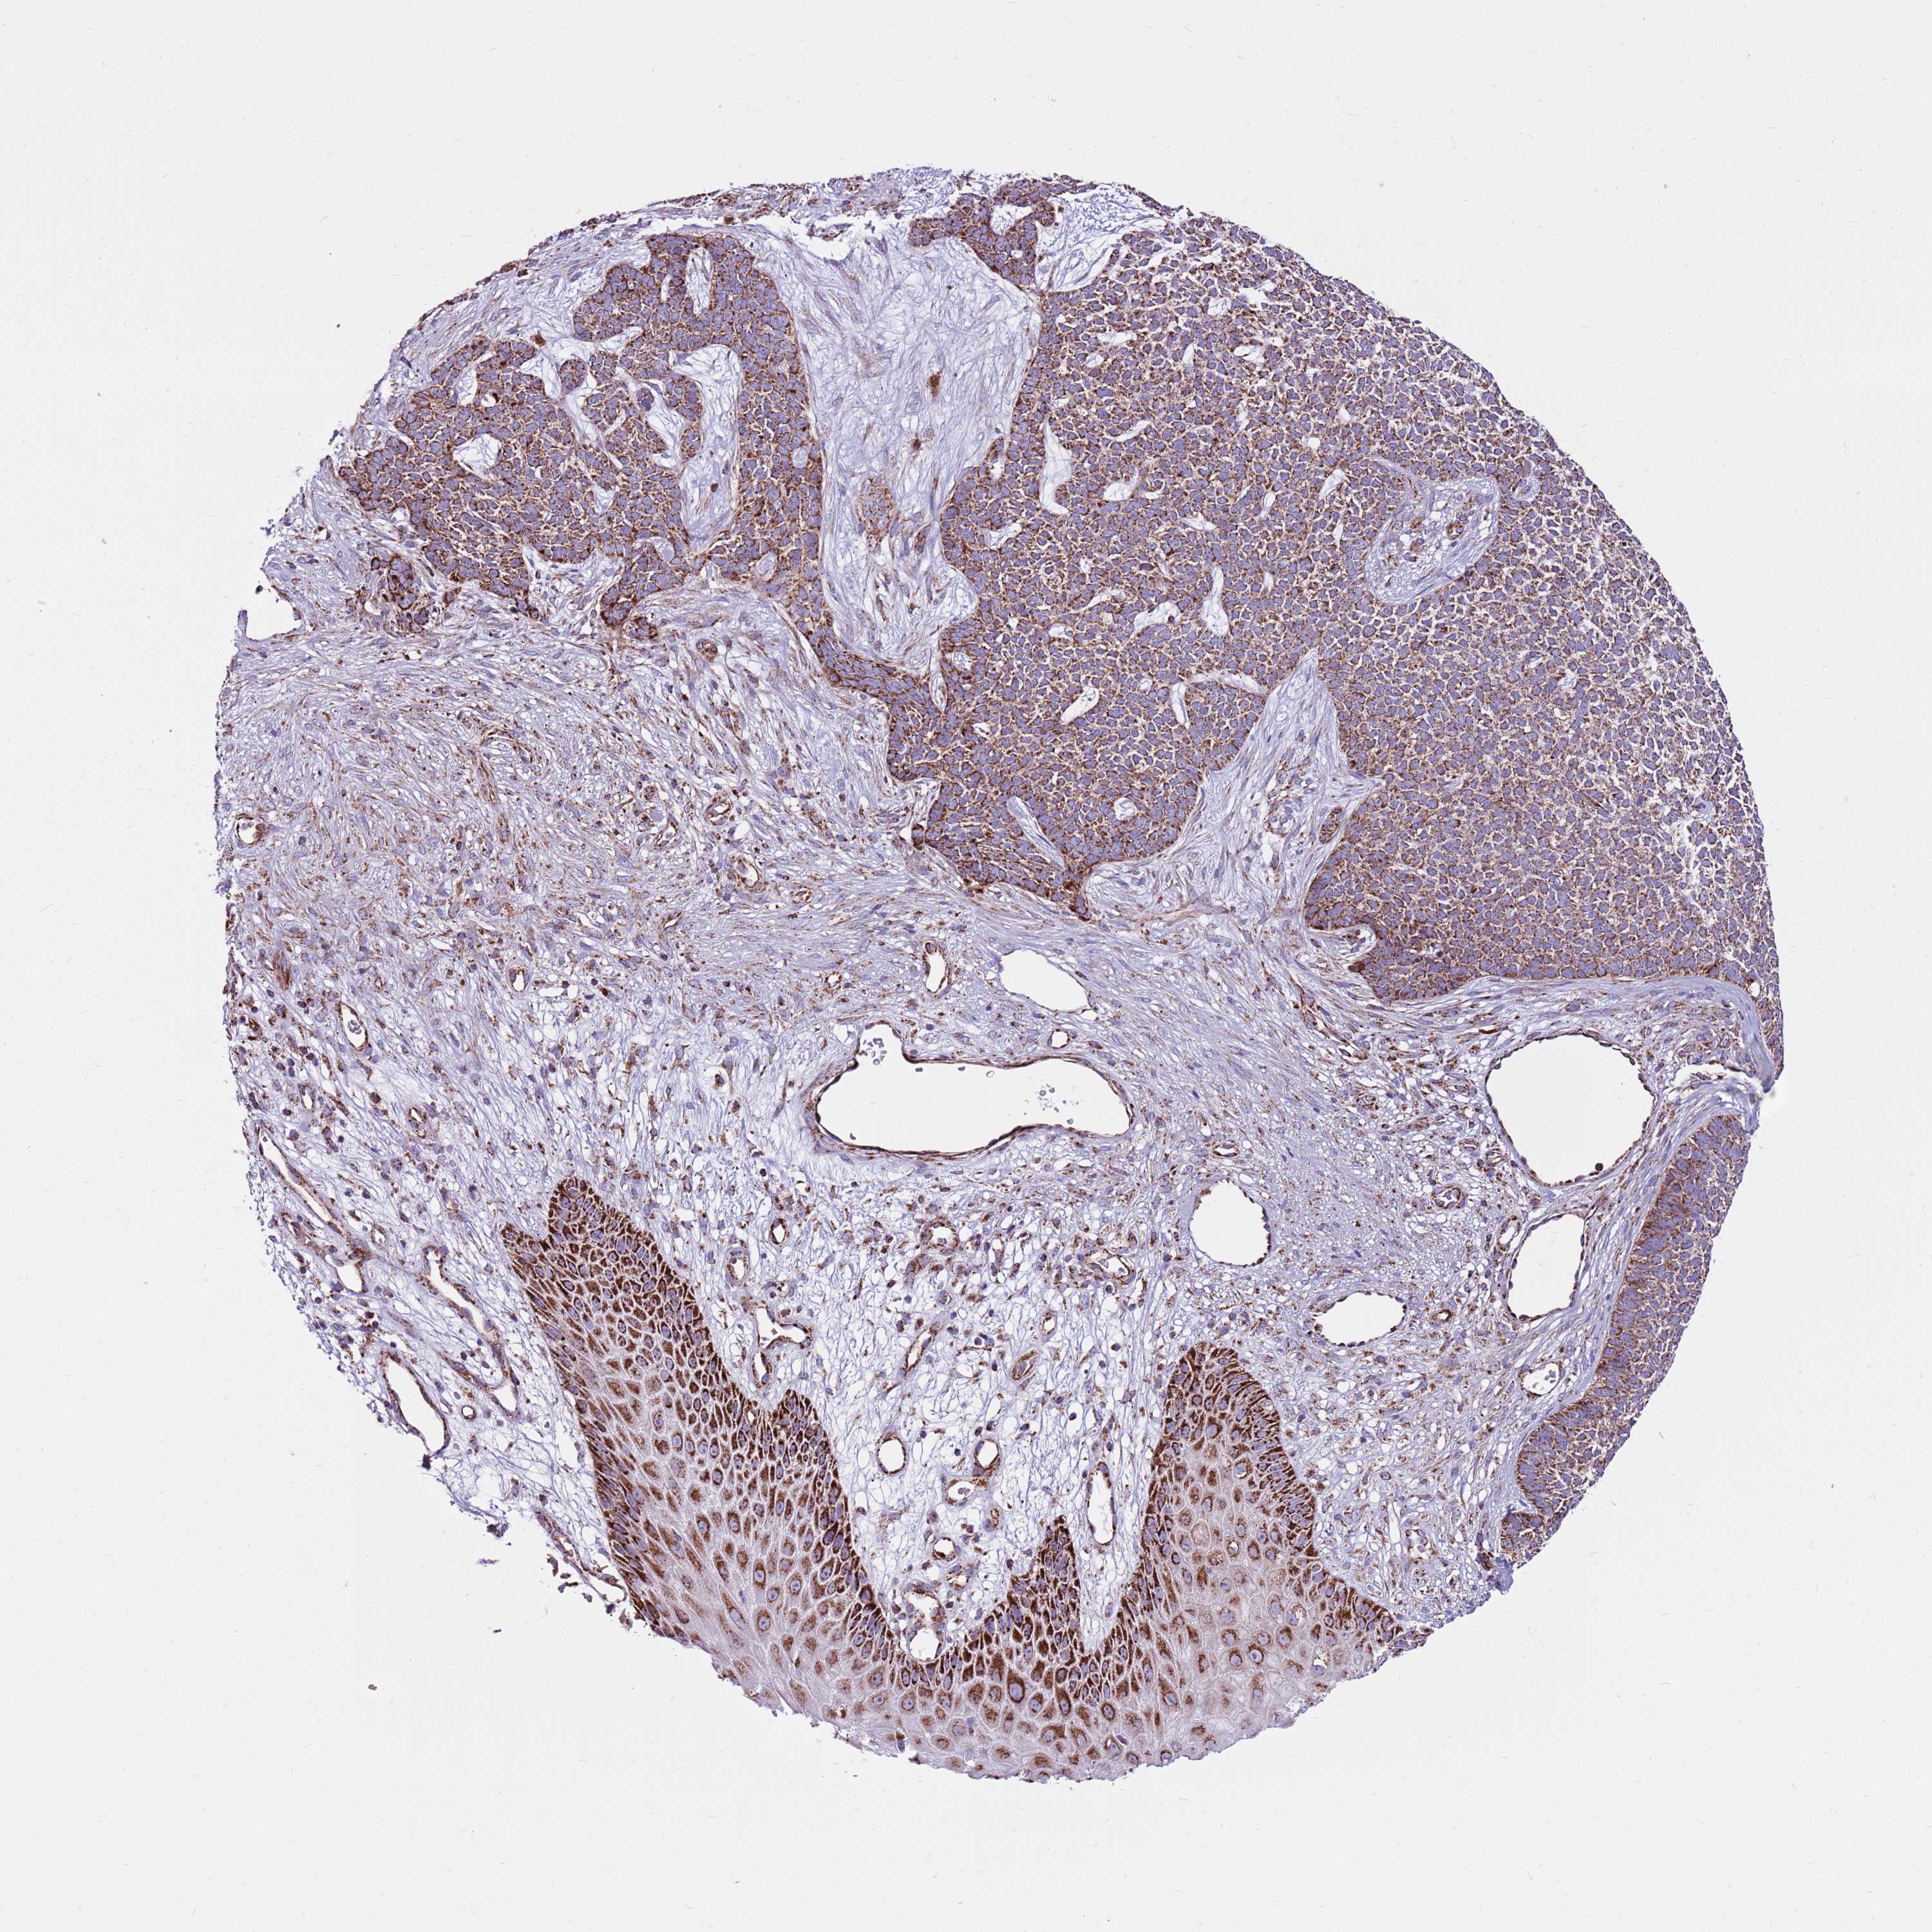

SKIN CANCER - Protein expressioni

A mouse-over function shows sample information and annotation data. Click on an image to view it in a full screen mode. Samples can be filtered based on level of antibody staining by selecting one or several of the following categories: high, medium, low and not detected. The assay and annotation is described here.

Antibody stainingi

Antibody staining in the annotated cell types in the current human tissue is reported as not detected, low, medium, or high, based on conventional immunohistochemistry profiling in selected tissues. This score is based on the combination of the staining intensity and fraction of stained cells.

Each image is clickable and will lead to virtual microscopy that enables deeper exploration of all samples and also displays staining intensity scores, fraction scores and subcellular localization as well as patient and tissue information for each sample.

Antibody HPA041062

Antibody HPA045473

Basal cell carcinoma

Squamous cell carcinoma, NOS

Squamous cell carcinoma, metastatic, NOS